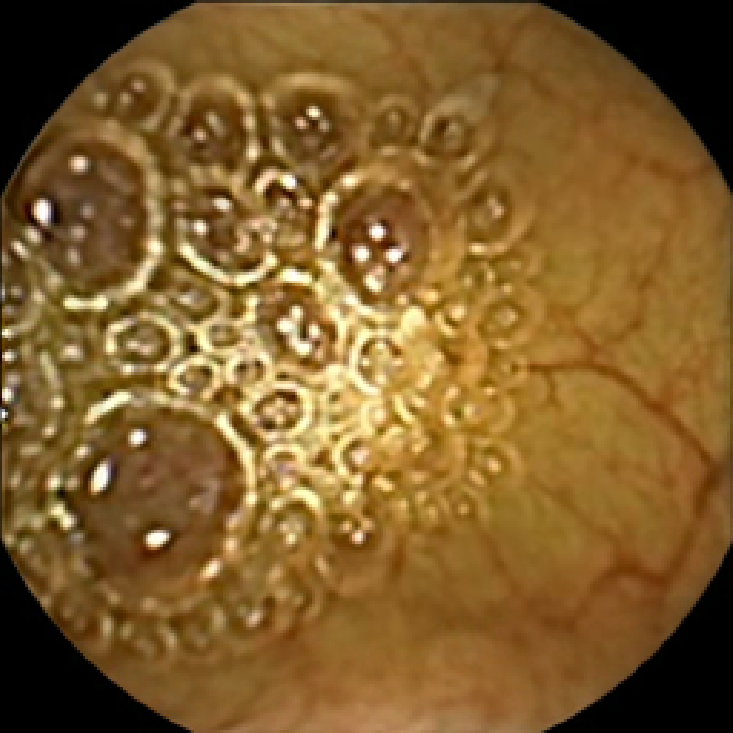

The lower bound filters out the frames with too little texture content that are unlikely to contain any polyps due to most polyps having a textured surface. The upper bound allows us to discard the frames polluted with trash and bubbles, since even if they contain polyps, they are likely to be obscured. This is illustrated in Figure 2, where we display two normal frames with low and high values of and a polyp frame with a medium value of . As expected, the first normal frame containing flat mucosa has little texture content. The second normal frame polluted with bubbles has strong texture content in the bubbles area, which is especially pronounced in the plot of . Finally, the polyp frame has moderately textured polyp area, which can also be easily observed from that has the strongest feature in that region.

We illustrate the above considerations in Figure 4, where we compare the ellipses of inertia for a polyp frame and two frames with pronounced mucosal folds. The ellipses we plot are

As expected, we observe that the ellipses corresponding to mucosal folds (feature 2 in the second row and features 2 and 3 in the third row of Figure 4) are indeed much more stretched out than the ellipse corresponding to a polyp (feature 1 in the first row of Figure 4). Stretched ellipses imply higher eccentricity, thus we impose the following criterion